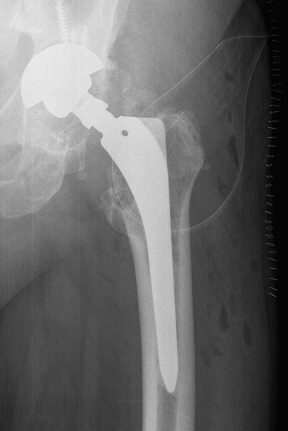

Fig. 4

Fig. 4.

Postoperative radiograph after second revision with four Dall-Milles cerclages.

In October 2013 (two years and one month after the revision procedure), the patient was surprised by a storm and was struck by lightning while strolling. He remained conscious and suddenly he was unable to bear weight on the left leg and a deformity on his left lower extremity was detected. His neurovascular status was stable. Plain radiographs demonstrated a displaced fracture through the base of the neck of the femoral component (Fig. 3 ). The patient underwent revision THA through a posterior iterative approach. A transfemoral osteotomy was required to extract the stem, which presented no signs of loosening. Prophylactic Dall-Miles wiring was done to prevent fractures just under the osteotomy. The selected component for the revision was a modular curve Revitan® (Zimmer, Winterthur, Switzerland) system. It was a 200 × 180 mm stem with a distal locking screw of 36 mm and a metaphysis of 75 mm with 15° of anteversion. The head was a #36 metallic. Finally, the osteotomy was fixed with four Dall-Miles cerclages (Fig. 4 ). After the surgery, the patient needed two blood transfusions due to postoperative anaemia. The postoperative course was otherwise unremarkable and the patient was allowed partial two-crutch assisted weight-bearing. The patient was discharged with an active range of motion of 75° of hip flexion and 15° of hip abduction. Three months after surgery, the radiographs demonstrated consolidation of the osteotomy. After one year, the patient is satisfied, without pain and had returned to work.